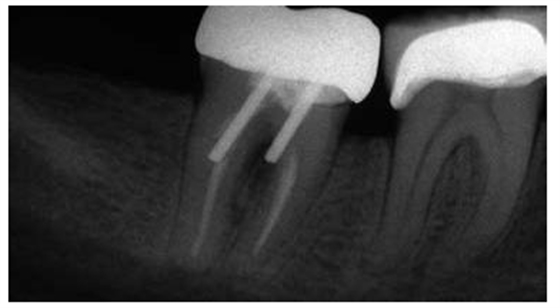

圖1:上頜第二前磨牙根折的根尖片,經(jīng)由預(yù)成金屬樁修復(fù)

圖2:上頜第一前磨牙的根尖片,過長的平行壁樁修復(fù),根尖部的牙膠量少于理想的5mm的根尖封閉

圖3:上頜第二前磨牙,牙根里非常短的樁

圖4:下頜第二前磨牙的根尖片,經(jīng)由螺紋樁進行修復(fù),導(dǎo)致根折

5:下頜第二磨牙牙根穿孔的根尖片,樁道預(yù)備的器械未與根管壁相平行